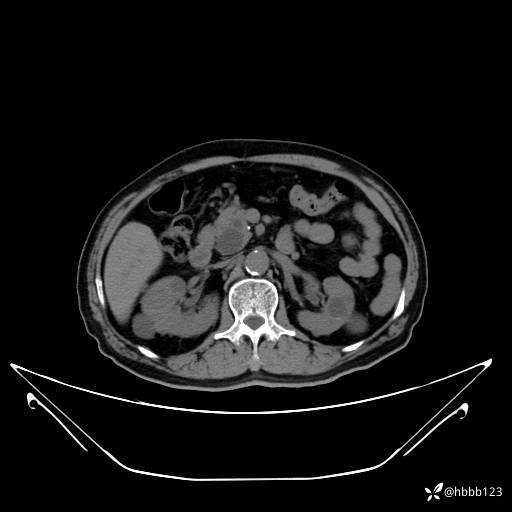

门诊完善上腹部CT平扫+增强扫描:

平扫: